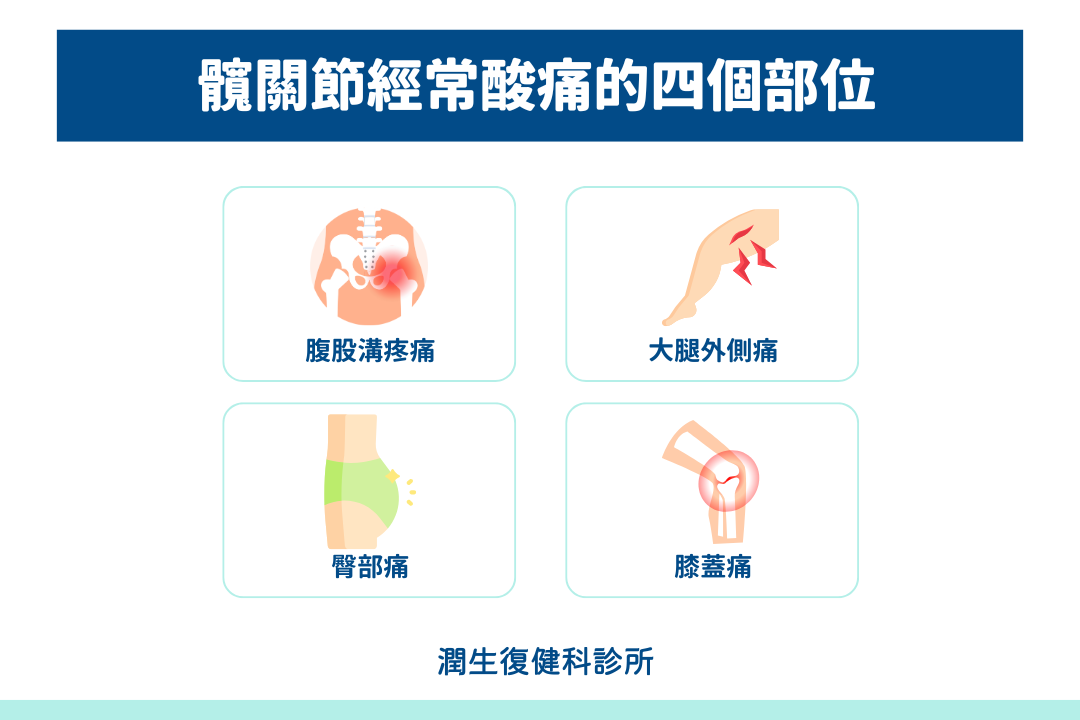

髖關節酸痛部位

髖關節疼痛的「欺騙性」在於,疼痛可能出現在多個不同位置,這常讓患者和醫師感到困惑:

腹股溝疼痛

腹股溝疼痛是髖關節炎最典型的表現,通常呈現深層悶痛,可能隨著活動增加而加劇。

這類疼痛往往影響日常動作,如行走或上下樓梯,患者可能感受到關節僵硬或不適。腹股溝疼痛很可能是來自髖關節內部問題的信號,如軟骨磨損或關節唇損傷。

大腿外側疼痛

大腿外側疼痛則可能與髖關節炎或髖外側肌腱炎有關,這類疼痛可能在長時間站立或行走後變得更明顯,甚至在夜間休息時也會感到不適。

患者常描述為持續的鈍痛或灼熱感,某些姿勢可能加重不適。

臀部疼痛

臀部疼痛在久坐後站立時特別明顯,許多患者會在改變姿勢時感受到強烈的不適,甚至需要片刻適應才能順利行動。

這類疼痛可能延伸至大腿後側,影響坐姿舒適度和行走能力。

膝蓋疼痛

膝蓋疼痛則是另一種常見但容易被誤判的情況。許多患者以為問題出在膝關節,實際上這種疼痛可能是由髖關節炎引起的轉移痛。

這類疼痛可能在活動時加劇,且經常伴隨髖部活動受限,影響整體行動能力。醫師通常需要仔細評估是否有髖關節問題引起的膝關節症狀。

了解髖關節疼痛可能出現的不同位置有助於更準確地描述症狀,幫助醫師作出正確診斷。許多患者因為疼痛位置與預期不同而延誤就醫,這是需要避免的情況。